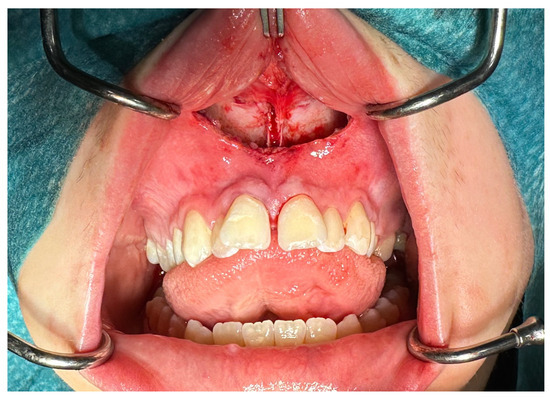

| No possibility of distraction—1 case | Maxillary incisor root resorption—2 cases |

| Palatal mucosal necrosis—2 cases | Bone loss/lack of adhesion in the distraction gap—5 cases |

| Perforation of the maxillary alveolar process caused by the distractor—1 case | Maxillary incisor necrosis—2 cases |

| Asymmetric distraction—5 cases | |